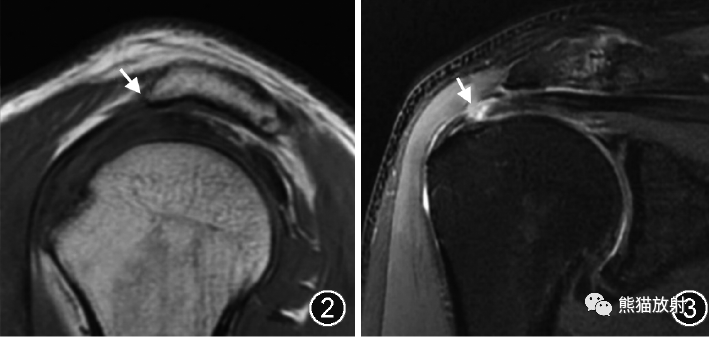

肩峰形态分为4型,Ⅰ型为扁平形,Ⅱ型为弓形,Ⅲ型为钩形,Ⅳ型为凸面向下的反弓形,其中Ⅲ型肩峰最易引起肩峰下撞击(图2,3)。

图2,3 Ⅲ型肩峰伴肩峰下撞击综合征的MR图像。肩关节MR平扫斜矢状面

图4 肩峰倾斜的MR图像。肩关节MR平扫斜矢状面T1WI示肩峰前部向前下倾斜(↑),肩峰下间隙狭窄